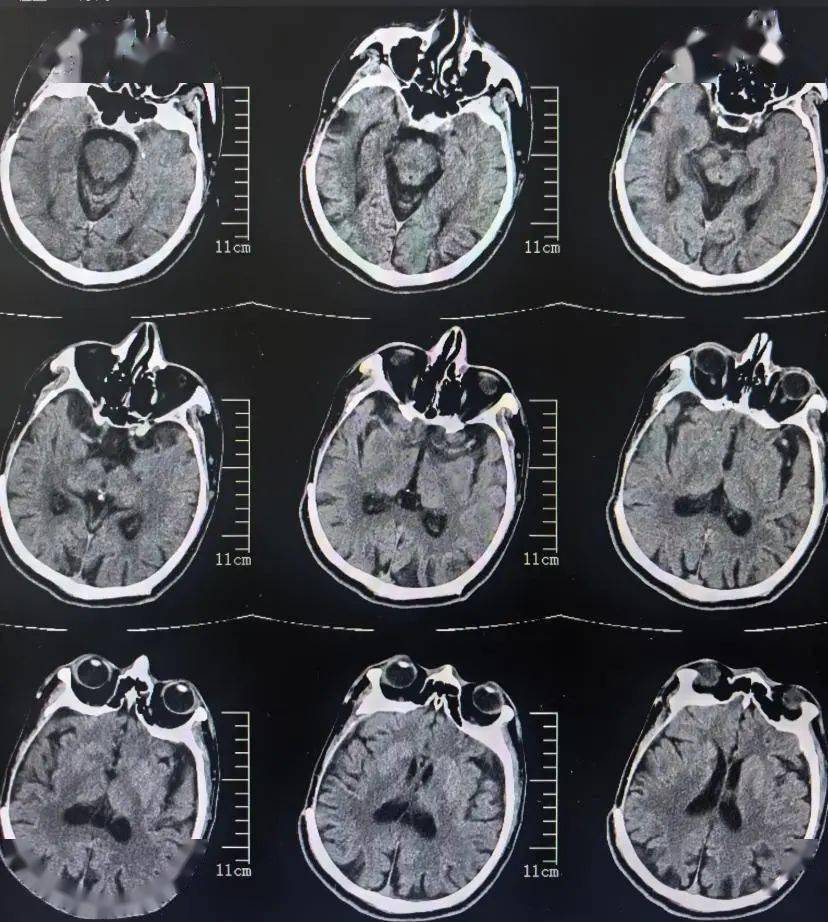

82岁脑出血后脑积水,北京某脑科医院治反致感染后19个月仍走路不稳

图-9:2018年1月11日头颅ct住院后9天即2018年1月17日,引流出淡黄色

7月31日拔除引流管,8月1日ct如下:7月28日ct,引流减少,夹闭引流管